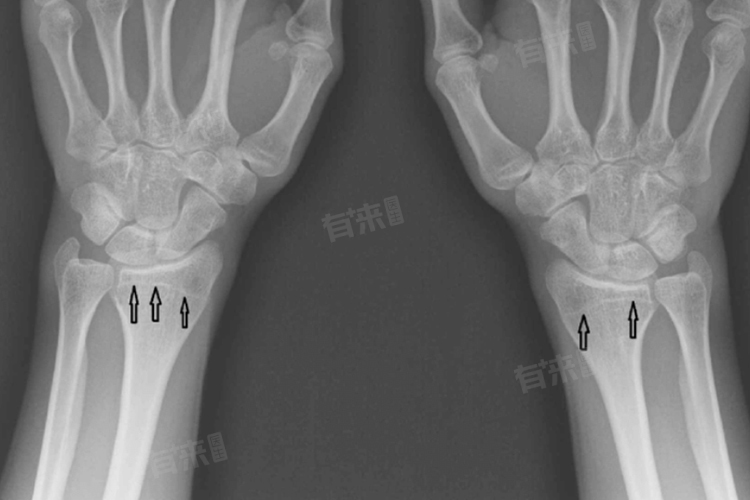

骨骺线闭合后,通常不能二次长高。这一结论基于骨骼生长发育的生理机制,即骨骺线是骨质生长的重要组成部分,位于长骨的两端,是骨骼纵向生长的关键区域。在生长发育期间,骨骺线不断分裂增殖,使骨骼得以延长,从而实现身高的增长。

- 随着年龄的增长,骨骺线会逐渐闭合,标志着骨骼的纵向生长停止,身高也就基本固定。这一过程是自然生长发育的必然结果,也是人体生长规律的重要体现。而骨骺线闭合是一个不可逆的生理过程,标志着人体骨骼生长发育的结束。因此,从生理和医学的角度来讲,骨骺线闭合后不能二次长高。